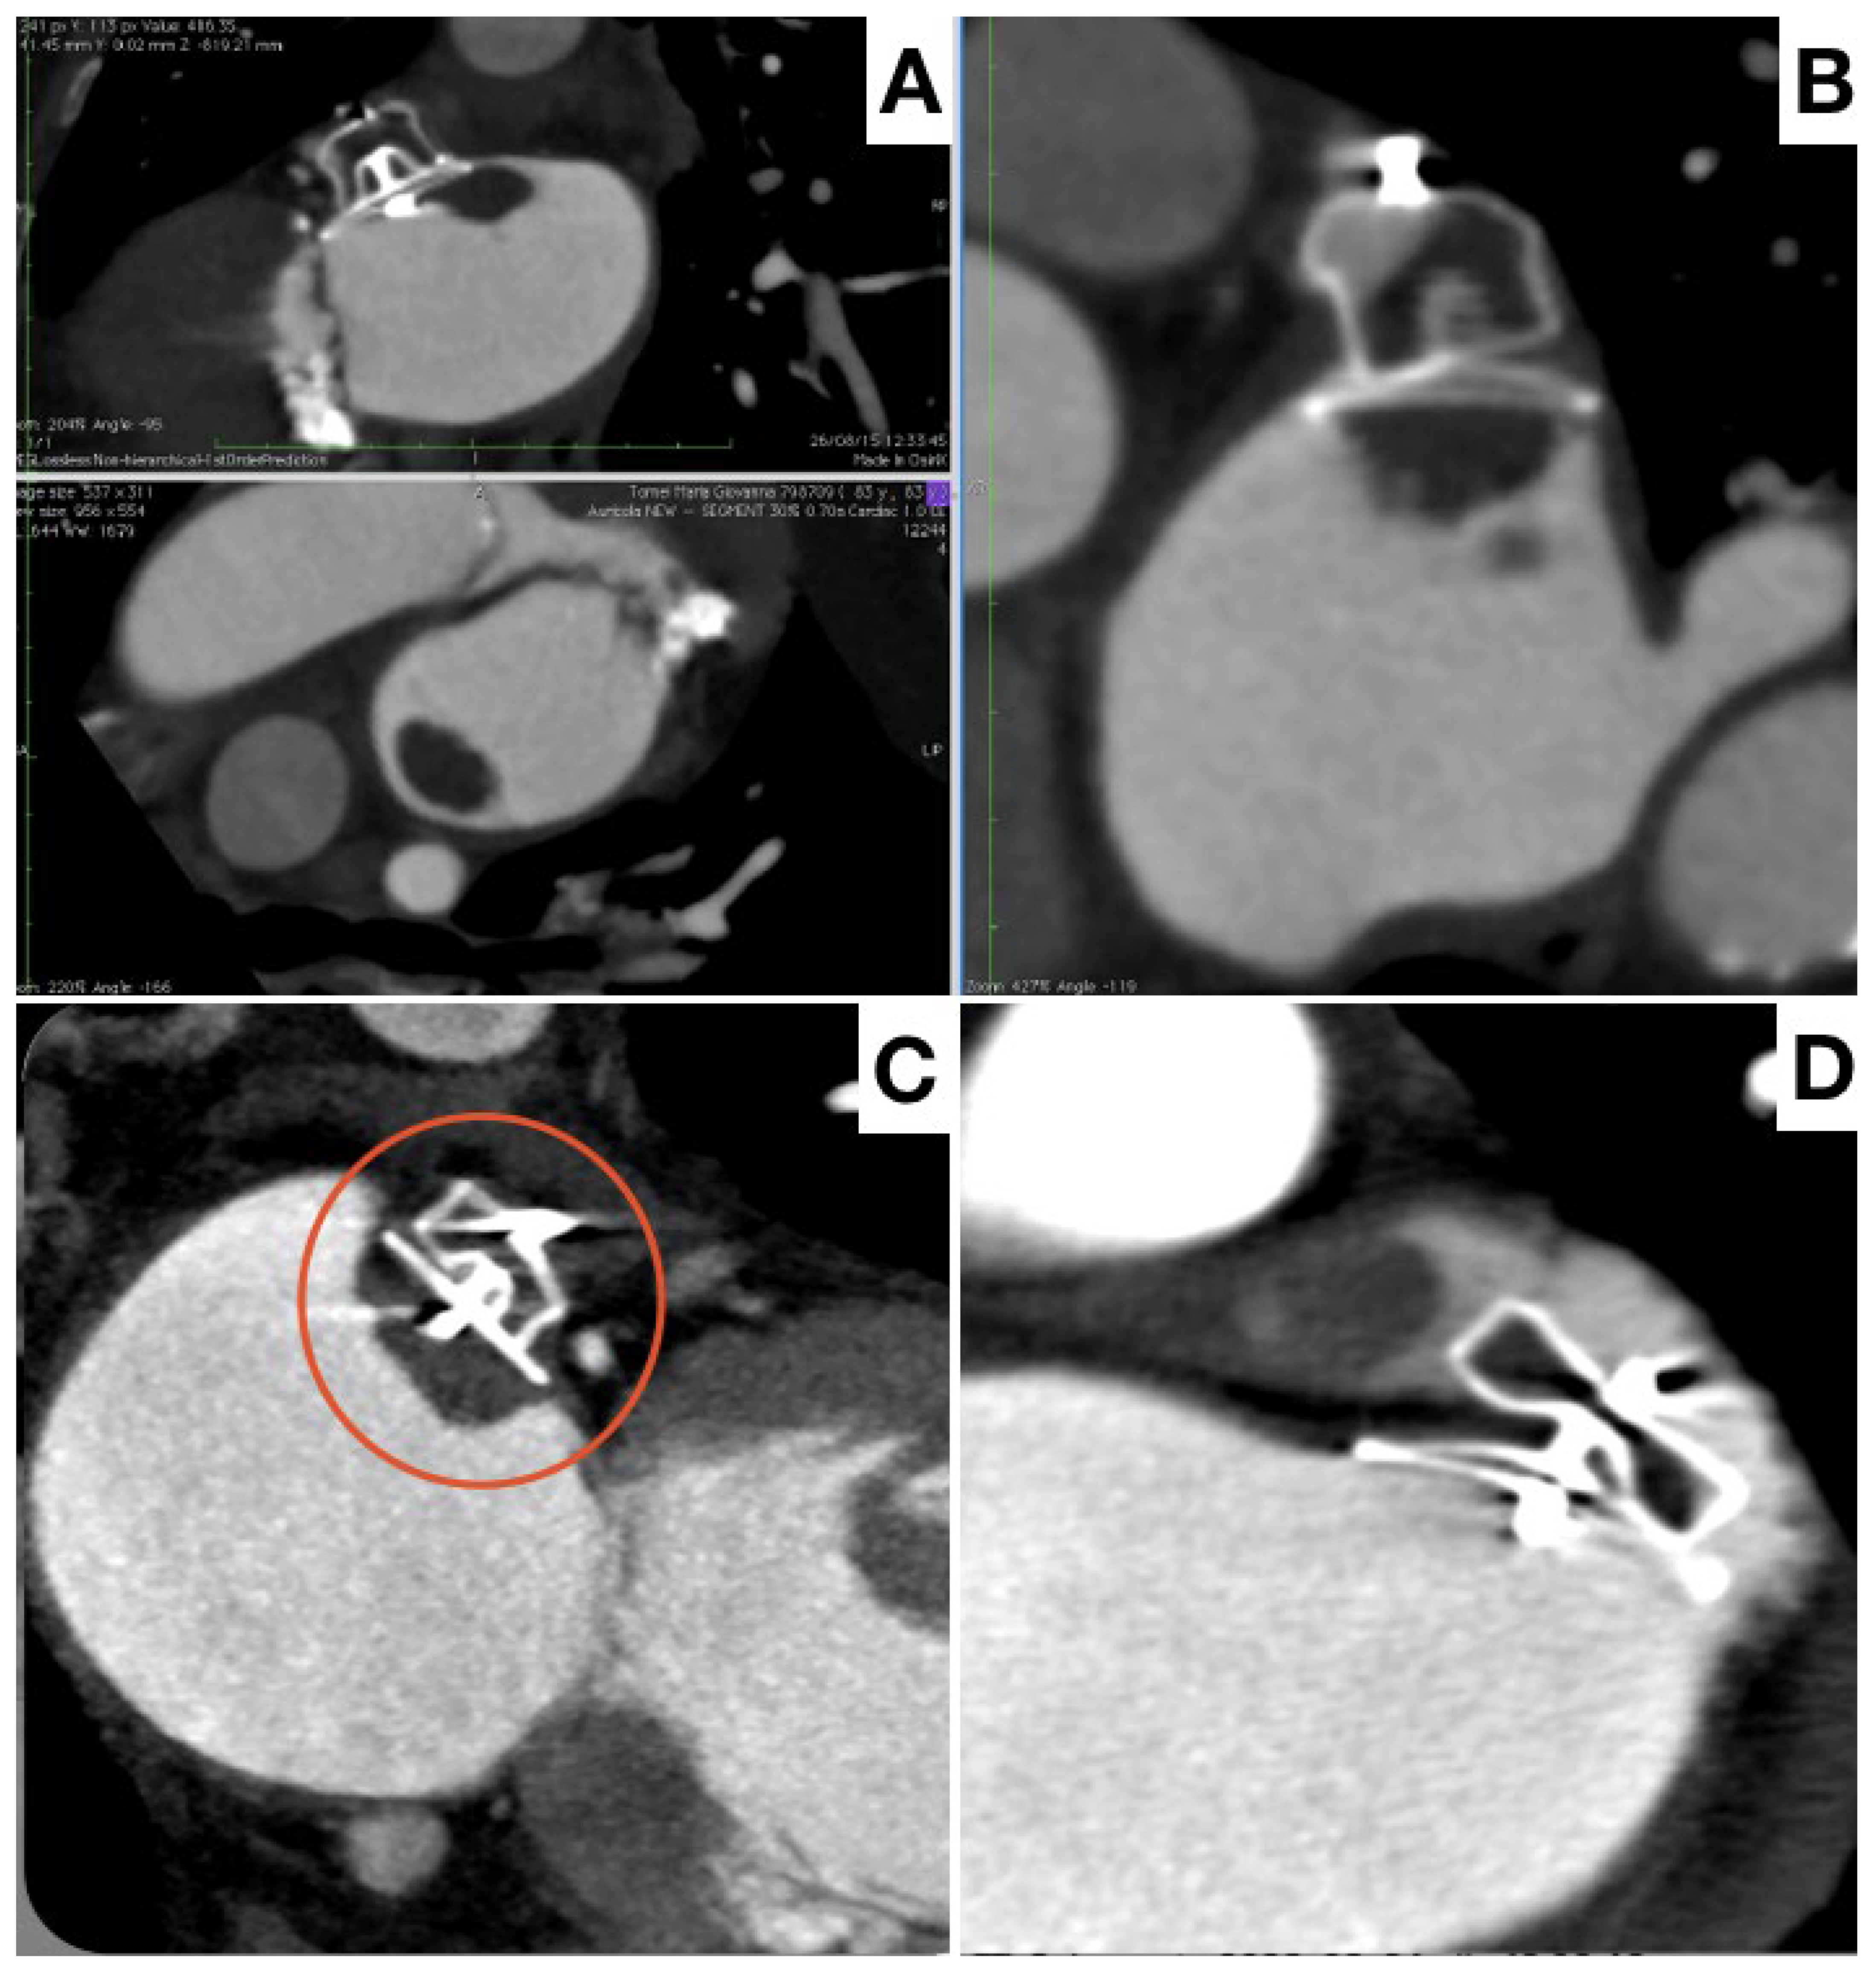

- Fukutomi, M.; Fuchs, A.; Bieliauskas, G.; Wong, I.; Kofoed, K.F.; Søndergaard, L.; De Backer, O. Computed tomography-based selection of transseptal puncture site for percutaneous left atrial appendage closure. EuroIntervention 2022, 17, e1435–e1444. [Google Scholar] [CrossRef]

- Wang, D.D.; Eng, M.; Kupsky, D.; Myers, E.; Forbes, M.; Rahman, M.; Zaidan, M.; Parikh, S.; Wyman, J.; Pantelic, M.; et al. Application of 3-Dimensional Computed Tomographic Image Guidance to WATCHMAN Implantation and Impact on Early Operator Learning Curve: Single-Center Experience. JACC Cardiovasc. Interv. 2016, 9, 2329–2340. [Google Scholar] [CrossRef]

- Clemente, A.; Avogliero, F.; Berti, S.; Paradossi, U.; Jamagidze, G.; Rezzaghi, M.; Della Latta, D.; Chiappino, D. Multimodality imaging in preoperative assessment of left atrial appendage transcatheter occlusion with the Amplatzer Cardiac Plug. Eur. Heart J. Cardiovasc. Imaging 2015, 16, 1276–1287. [Google Scholar] [CrossRef]

- Korsholm, K.; Jensen, J.M.; Nørgaard, B.L.; Samaras, A.; Saw, J.; Berti, S.; Tzikas, A.; Nielsen-Kudsk, J.E. Peridevice Leak Following Amplatzer Left Atrial Appendage Occlusion: Cardiac Computed Tomography Classification and Clinical Outcomes. JACC Cardiovasc. Interv. 2021, 14, 83–93. [Google Scholar] [CrossRef]